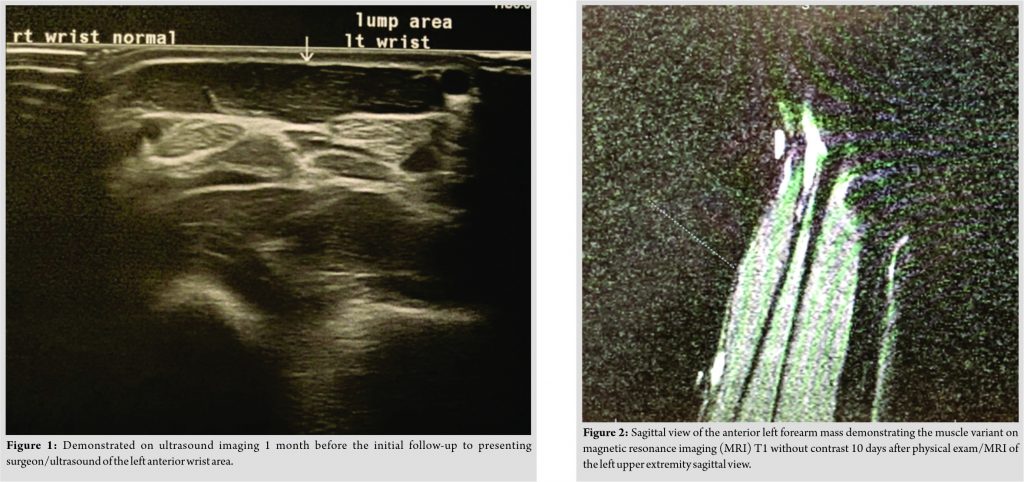

A right hand dominant, 28-year-old Caucasian male presented to the orthopedic associates of Southwest Ohio as a referral to a hand specialist due to an abnormal ultrasound finding and left wrist mass. The ultrasound of the suspected left wrist mass was executed 10 days prior, exhibiting increased echogenicity within the musculature of the left distal wrist at the site of the patient’s reported abnormality. This echogenicity was asymmetric when compared to the right wrist. The image of the left anterior distal forearm on ultrasound is displayed in Fig. 1. There was no evidence of a focal mass or fluid collection according to the ultrasound report. The patient presented complaining of left wrist swelling, with no pain. There was an unremarkable past medical, surgical, or family history significant to the chief complaint. As far as a differential, the questionable echogenicity within the musculature of the left distal forearm could have been related to a mild non-specific myositis. Moreover, there was no evidence of focal mass or fluid collection, so an MRI was considered to rule out a neoplasm. The patient completed the MRI in 10 days, and then followed up in a week to the clinic. The current status of the patient remained unchanged. The MRI of the patient demonstrated a palpable abnormality secondary to a congenital variation consisting of a PL muscle variant due to an accessory muscle belly volar to the flexor tendons. The signal intensity of this muscle appears within normal limits. This finding was confirmed on the retrospective review of the prior ultrasound. The abnormal muscle variant is displayed in the sagittal view T1 MRI in (Fig. 2), it is displayed in the coronal view T1 MRI in (Fig. 3), and it is displayed in the coronal view T2 MRI in (Fig. 4).

In the present case, the PL muscle belly originated at the distal forearm volar to the flexor digitorum profundus and superficialis tendons. The abnormality lied between the soft tissue markers placed at the site of the patient’s complaint of the palpable abnormality.